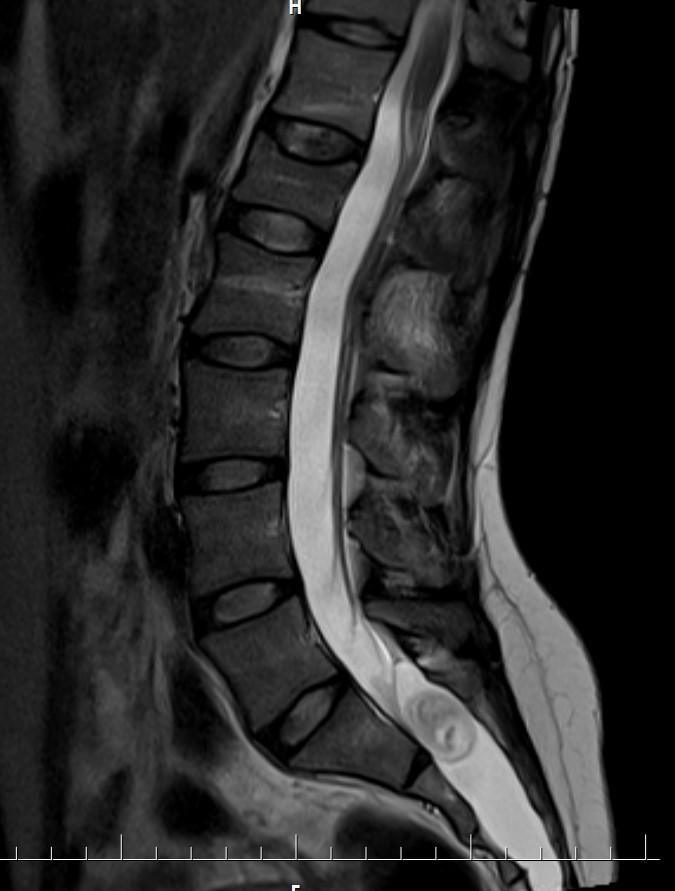

Answer: Occult intrasacralmeningocele

MR images demonstrated large cystic lesion in the sacral canal.

Occult intrasacralmeningoceletypically appear hypodenselesion (isodense to CSF) enlarging the sacral thecal sac which may displace the nerve roots.

MRI is the best modality to assess an occult intrasacralmeningocele.

• T1: hypointense(isointense to CSF)

• T2: hyperintense (isointense to CSF)